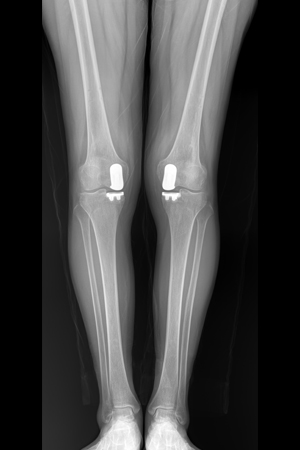

SNU서울병원의 ‘로봇인공관절 수술’은 최선의 무릎 치료를 위해 추진해 온 과감한 의료시설 투자 중 하나로 S사의 마코(MAKO)와 Z사의 로사(ROSA)를 두 대 보유하여 1:1 환자 맞춤용 인공관절로 더욱 정확하고 안전한 진료를 제공하고 있습니다.

로봇인공관절 수술은 의사의 수술 노하우와 로봇의 정확성이 결합된 최첨단 무릎 인공관절 수술입니다. 수술 전 CT 검사 후 로봇이 검사 결과를 3D 화하여 환자의 무릎 상태를 정확히 파악한 후, 세밀한 수술 계획을 제안합니다. 그리고 의사가 로봇암(Robot Arm)을 잡고 정밀하게 뼈를 절삭한 후 최적의 인공관절을 삽입하는 수술 방법입니다. 컴퓨터 프로그램으로 환자의 무릎 상태를 정확히 파악한 후 로봇수술 집도 인증을 받은 정형외과 전문의가 집도하므로 수술의 위험도가 적고 연부 조직의 손상을 최소화할 수 있는 장점이 있습니다.

X-Ray 검사

환자의 뼈 크기와 상태에 맞는 최적의 인공관절 삽입